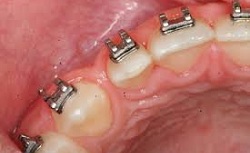

Treatment Phase(Bonding of braces onto the teeth).

In this phase we bond the braces onto the individuals teeth. You are then required to come for a check-up and adjustments every 30 days. Evaluation of progress is vital. A deposit of 30% towards the procedure is made before the treatment starts, the remaining 70% is payable within 24 months in installments.